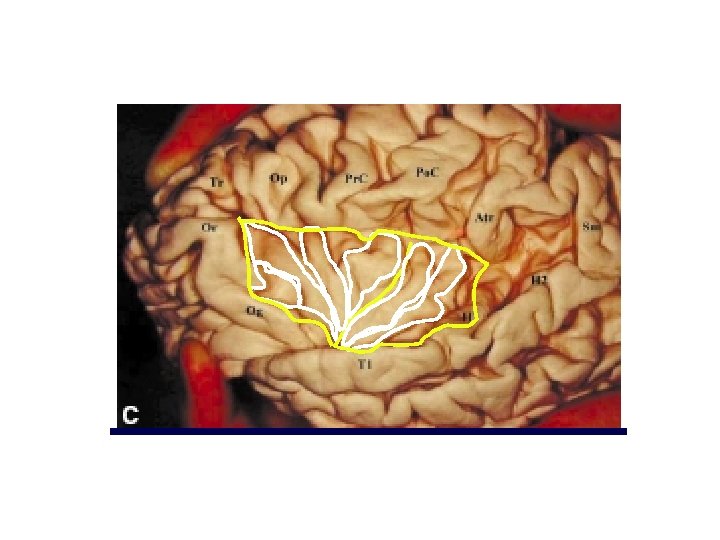

M. G. Yasargil lesionectomy for insular tumors 1) Removal of the central zone performing a longitudinal sulcus incision 2) Debulking of infero-anterior zone 3) Debulking of the inferior region 4, 5, 6) Once obtained room enough: antero-superior, superior and posterior 7) Removal of the region in the limen insula